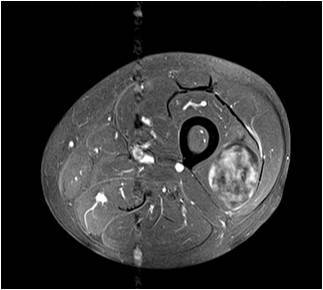

Physician Assistant Lower Limb and Thorax Written Examination - Radiology Pool

Gallery of Unlabled Radiographs from Lecture (Dr. French) - 2020

Click a thumbnail to enter the gallery display. Click the file name link at the bottom left of the gallery display to view the image at high resolution.